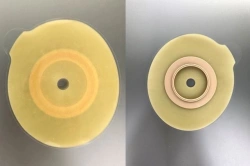

Medical product is intended for use in colostomies, ileostomies and urostomies for hermetic and secure attachment of stoma bags to the skin of the anterior abdominal wall, as well as to protect the skin of the peristomal area from stoma secretions and preserve the physiological functions of the skin due to the absorption of natural skin moisture (sweat, sebum).